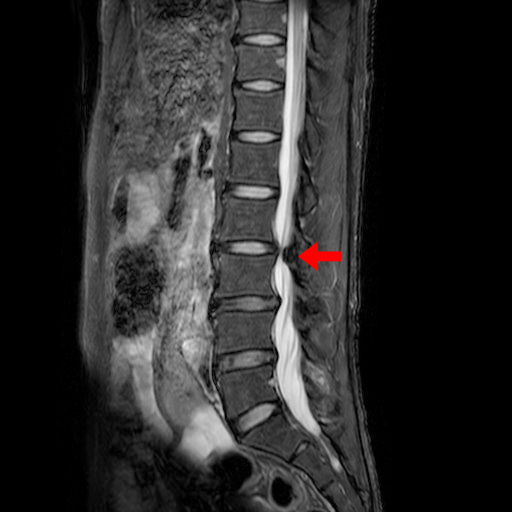

下記は私の腰のMRI画像です。

クリニックにデータが届く日に受診した結果は腰椎の椎間板ヘルニアでした。

同じ体勢でいると右足のみ軽い痺れも出てきていて力が入りにくい感覚があり、

ヘルニアといってもいろいろな状態があるので一概にどうとか言えないみたいですが

「めちゃくちゃ重度というわけではない」と言われました。